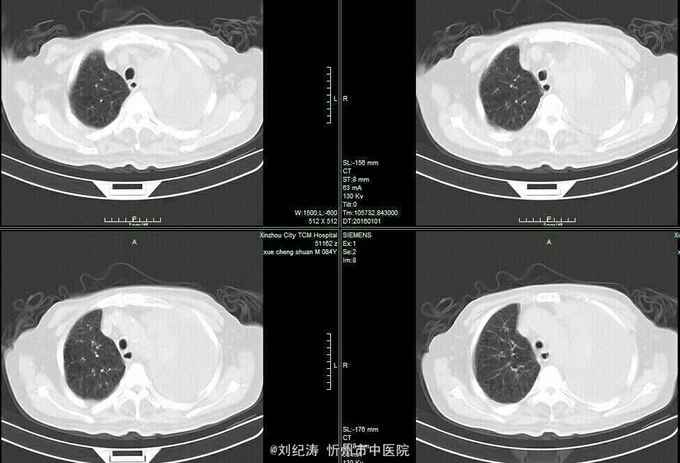

查体:ECOG评分:3分,生命指征平稳,浅表淋巴结未触及明显肿大,双眼睑无水肿,唇无发绀,颈软,双侧胸廓对称,左肺语颤增强,左肺呼吸音消失,右肺呼吸音粗,可闻及哮鸣音,心律齐,腹平软,肝脾肋下未触及,移动性浊音阴性,肠鸣音3次/分,双下肢无水肿。 辅助检查:血常规(2016.1.1):WBC:10.6*109/L,RBC:4.69*1012/L, PLT:165*109/L ,HGB:167g/L.生化(2016.1.1):谷丙转氨酶11U/L,谷草转氨酶11U/L,总蛋白60g/L,白蛋白33g/L,尿素:9.8mmol/L,肌酐:123umol/L,尿酸:251 umol/L,血糖:7.37 mmol/L;电解质:钾:4.79mmol/L,钠:123.5 mmol/L,氯:85.7 mmol/L,钙:2.03 mmol/L。肺部CT(2016.1.1):左肺完全萎缩,左侧胸腔大量积液,右肺未见异常,纵膈轻度右移,未见明显肿大淋巴结。